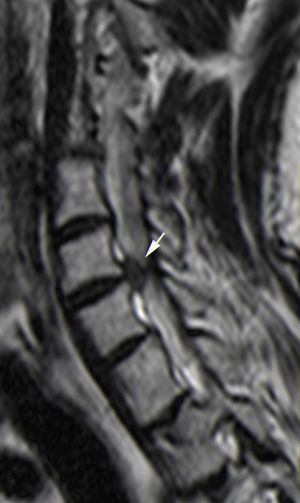

Se han intentado buscar métodos de imagen que permitan valorar e incluso prever si se va o no a desarrollar mielopatía. Existen diferentes clasificaciones para diagnosticar estenosis de canal, ya que es un tema controvertido y en constante evolución. Los primeros se basaron en radiografías laterales de columna cervical y se utilizaba la medida del diámetro anteroposterior del canal espinal cervical (fig. 1)33. La RM permitió no solo ver las estructuras óseas sino el componente del resto de las estructuras, especialmente combinando los planos sagitales y axiales. La detección de los pacientes con estenosis leve de canal tiene importancia, puesto que son propensos a desarrollar un mayor grado de estenosis y mielopatía. La compresión en secuencias T1, como la obliteración de la columna de LCR en secuencias T2 o los cambios de señal intramedulares son importantes34–37 (fig. 13).

Estenosis de canal y mielopatíaLa estenosis de canal cervical puede ser secundaria a componente discal, ligamentario u óseo pero con frecuencia se debe a la combinación de los mismos. La gravedad del desplazamiento de la médula se ha relacionado con la gravedad de los síntomas clínicos. La compresión progresiva de la médula espinal se asocia al desarrollo de lesión medular secundaria a la compresión y mielopatía cervical degenerativa. La cirugía de descompresión medular es el pilar en el tratamiento de la mielopatía cervical degenerativa; sin embargo, sigue siendo controvertido saber cuáles son los factores pronóstico. Se valoran la edad, la duración de los síntomas, el estado neurológico preoperatorio, el tamaño, los cambios de intensidad de señal intramedular en RM en secuencias T2 o los potenciales evocados somatosensoriales33–37.